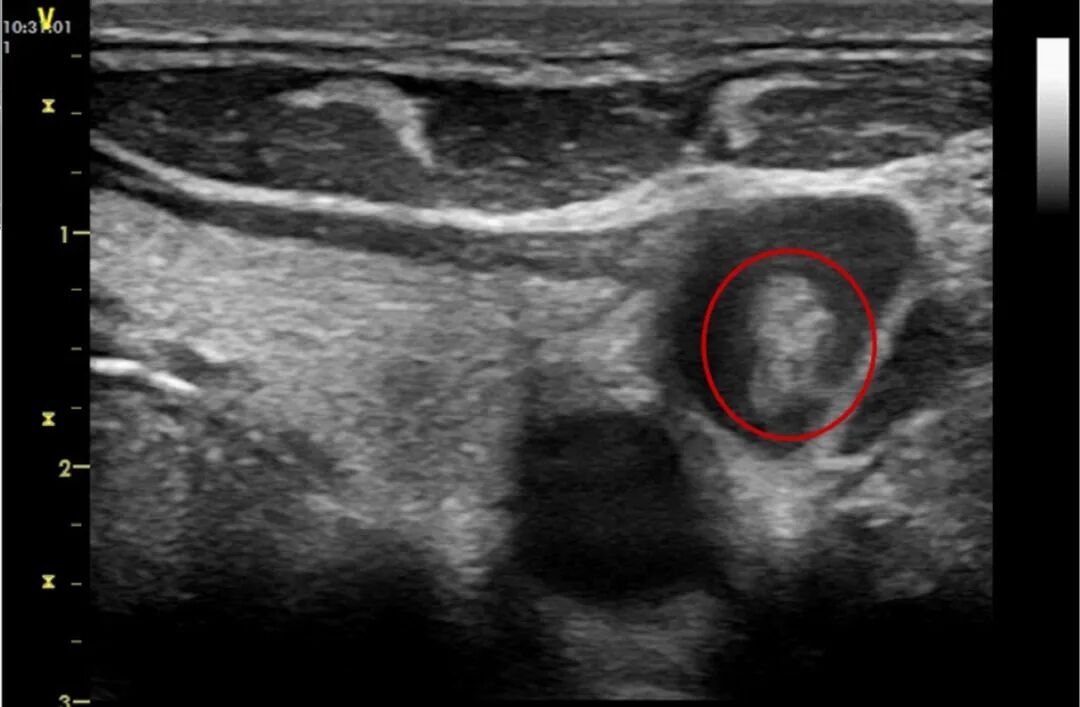

19岁男性,军人,既往体健。呕吐、呼吸困难20余日,加重3天,呼吸困难进行性加重并出现Ⅰ型呼吸衰竭,先后予以抗细菌、抗真菌、抗病毒、糖皮质激素等治疗无好转后转至我院。CT示双肺弥漫磨玻璃样改变,插管后次日气胸。超声可见右颈内静脉内中等回声条状影,基底相对较宽。追问病史患者在外院曾于颈内静脉留置深静脉导管,转院前已拔除。考虑患者存在导管相关的静脉血栓,短期内应避免在此处再行血管穿刺。

图片